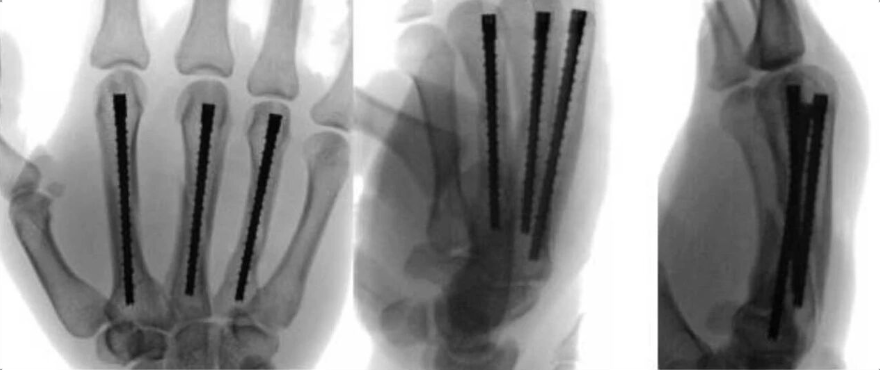

手外伤处理原则专题课程

71分钟

3.6万人学习